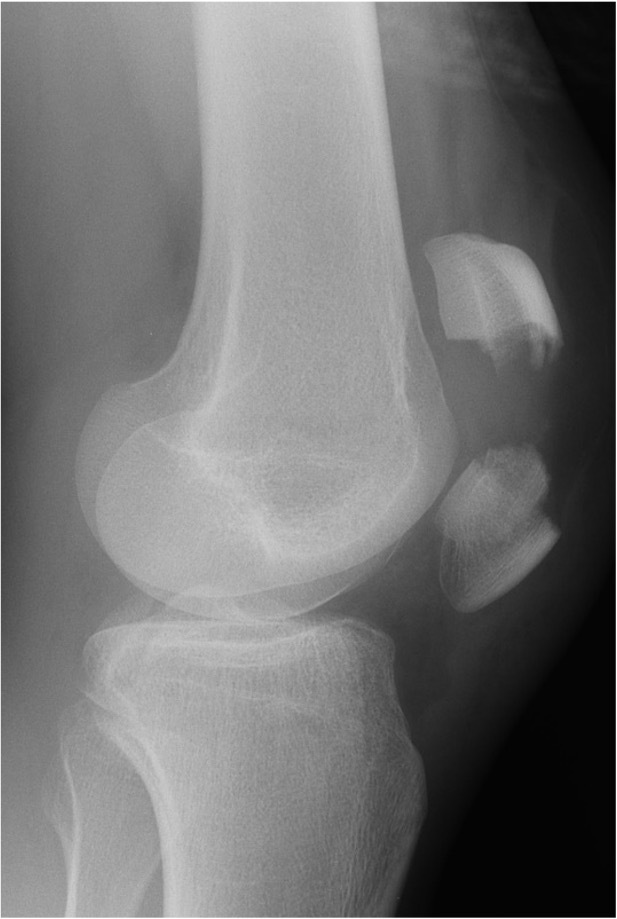

30 yo

RTA 60 mph- significant damage to the car

Hit the knee in the dash board

Pain++

Tender over patella

What is this ?

Patella fracture

The quads muscles commonly pull this muscle up seperating the two.